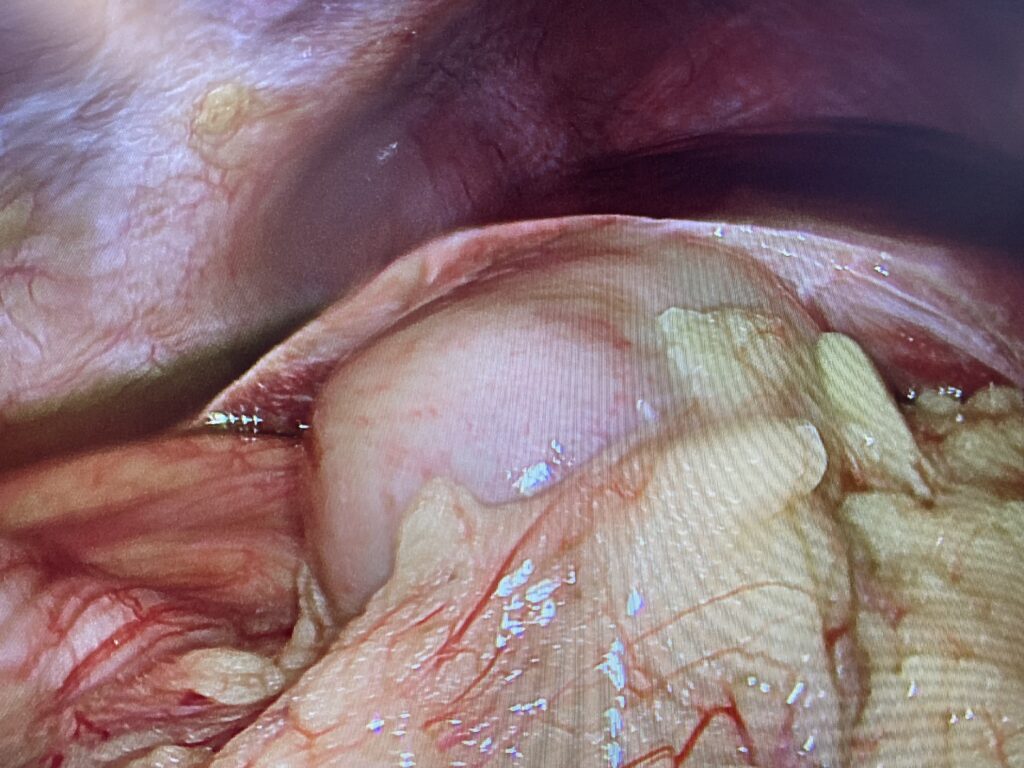

img 3603

Inflammed Gallbladder.……. But great picture!